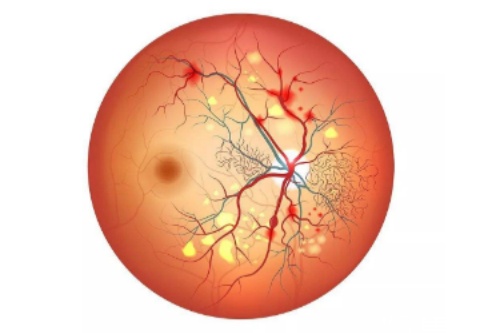

糖尿病视网膜病变,也被称为糖尿病性视网膜病变或糖网病。它是由于糖尿病导致视网膜微血管受损,进而影响视力。

随着病情的发展,患者可能出现视力下降、视物模糊、眼前黑影等症状,重度时甚至会导致失明,给患者的生活和工作带来极大不便。